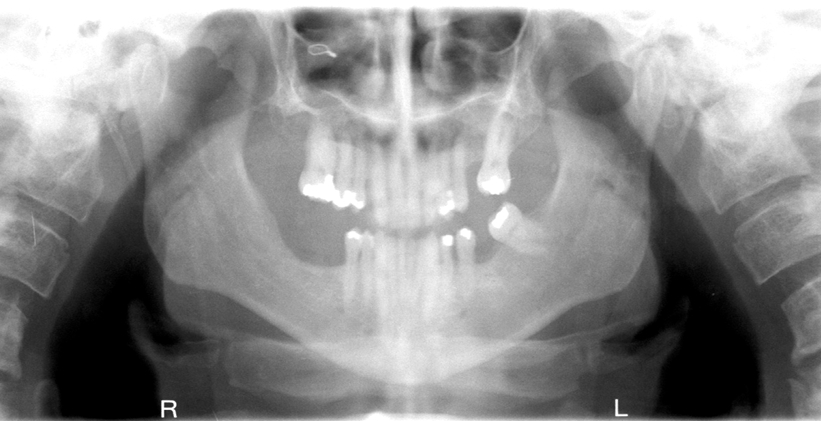

What is wrong with this image?

A

glasses